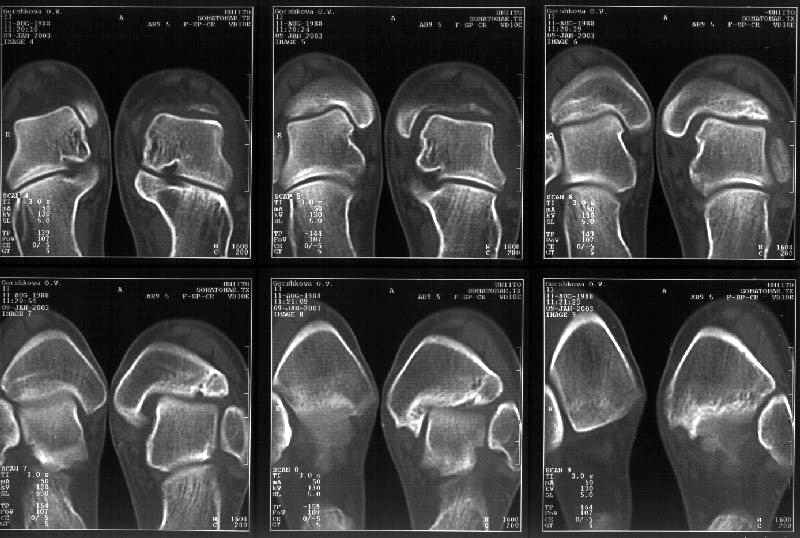

Мне в тоже время совершенно ясно видно по той же КТ, по 4 срезам, расположенным в центре и вверху пленки, что перелома внутренней лодыжки не было, в следующем собщении я приложу увеличенный фрагмент томограммы. А к этому письму прилагаю увеличеный фрагмент послеоперационной рентгенограммы, где выделил отколотый фрагмент

позади внутренней лодыжки. И он, как я вижу, находится между стержнем и тараном. А перелома внутренней лодыжки, и тем более смещения, IMHO

не определяется.

Здесь 4 среза, начиная от основания лодыжки и проксимальнее. Где, по Вашему мнению, проходит линия перелома, отделяющая переднюю часть внутренней лодыжки от большеберцовой кости? Заранее спасибо.

Сегодня пациентке сделали сравнительную КТ. А ксиальные и Фронтальные срезы приложены. Ваше мнение?

Фронтальные

Аксиальные

На КТ я попытался изобразить скромными своими способностями (А)- место перелома, (С)- нормальный суставной зазор меж тараном и тремя его маллеолами. (В)- образовавшийся в результате перелома широкий раза в три зазор, позволяющий, по-моему, сублюксацию тарана при ходьбе. В свете данных КТ, критически важных, я бы предложил вертикальную остеотомию места перелома

задне-внутренним подходом и фиксацию мед. маллеола прижатым к тарану с помощью тонкого compression screw. После этого гипсовый сапожок и немедленное расхаживание ноги.